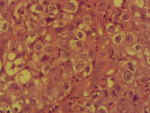

Démarche diagnostique: la démarche diagnostique a débuté par un examen gynécologique complet suivi de biopsies cervicales initiales. En raison d'une discordance entre les données cliniques et la première biopsie, une relecture anatomopathologique associée à de nouvelles biopsies a été demandée. L'examen histologique a montré une prolifération tumorale faite de massifs solides avec de rares structures glandulaires, constituée de cellules polygonales à cytoplasme clair ou éosinophile modérément abondant, avec des atypies cytonucléaires marquées et de nombreuses mitoses. Le stroma était fibro-œdémateux avec congestion vasculaire et suffusions hémorragiques, sans signe de différenciation malpighienne (Figure 1, Figure 2). L'étude immunohistochimique a montré une expression nucléaire focale de p16, sans expression de p63 ni de P40, confirmant un adénocarcinome à cellules claires du col de l'utérus. La tomodensitométrie thoraco-abdomino-pelvienne n'a pas mis en évidence de métastases, tandis que l'IRM abdomino-pelvienne a montré une tumeur cervicale localement avancée avec adénopathies iliaques externes gauches (Figure 3, Figure 4). Les diagnostics différentiels envisagés comprenaient un carcinome épidermoïde du col de l'utérus et d'autres types d'adénocarcinomes cervicaux. Les données histopathologiques et immunohistochimiques ont permis d'écarter ces hypothèses et de retenir le diagnostic final de carcinome à cellules claires du col de l'utérus.

Figure 2: détails cytologiques de la prolifération tumorale; cellules éosinophiles et claires hautement atypiques, avec des noyaux hyperchromatiques et de nombreuses mitoses, x400